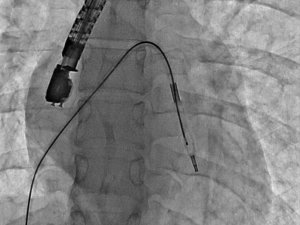

Mitral balon operasyonu adım adım kaydedildi